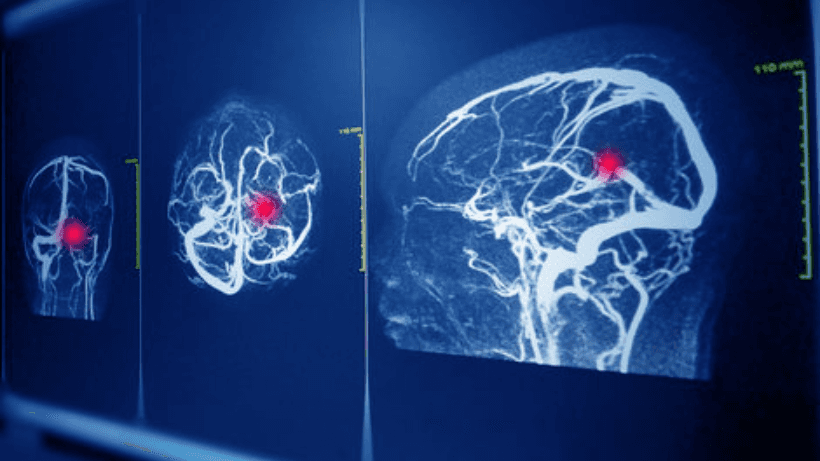

এ. ইমেজিং পরীক্ষা: এগুলি এমন গোয়েন্দা সরঞ্জামগুলির মতো যা ডাক্তাররা আপনার মস্তিষ্কের ভিতরে কী ঘটছে তা দেখতে ব্যবহার কর.

- সিটি স্ক্যান: এটি একটি উচ্চ প্রযুক্তির এক্স-রে এর মতো যা চিকিত্সকদের আপনার মস্তিষ্কের বিশদ ছবি দেয. এটি দ্রুত এবং প্রায়ই নির্ণয়ের জন্য প্রথম পছন্দ.

- এমআরআই: এটি আরও একটি ইমেজিং পদ্ধতি যা বিস্তারিত মস্তিষ্কের চিত্র তৈরি করতে চৌম্বক এবং রেডিও তরঙ্গ ব্যবহার কর. এটি বিশেষ করে ছোট অ্যানিউরিজম দেখানোর ক্ষেত্রে ভাল.

- সেরিব্রাল অ্যাঞ্জিওগ্রাফি: এটিকে আপনার রক্তনালীগুলির রোড ম্যাপ হিসাবে ভাবেন. একটি বিশেষ রঞ্জক আপনার রক্ত প্রবাহে ইনজেকশন করা হয়, এবং এক্স-রে কোনো অ্যানিউরিজমকে চিহ্নিত করতে নেওয়া হয.